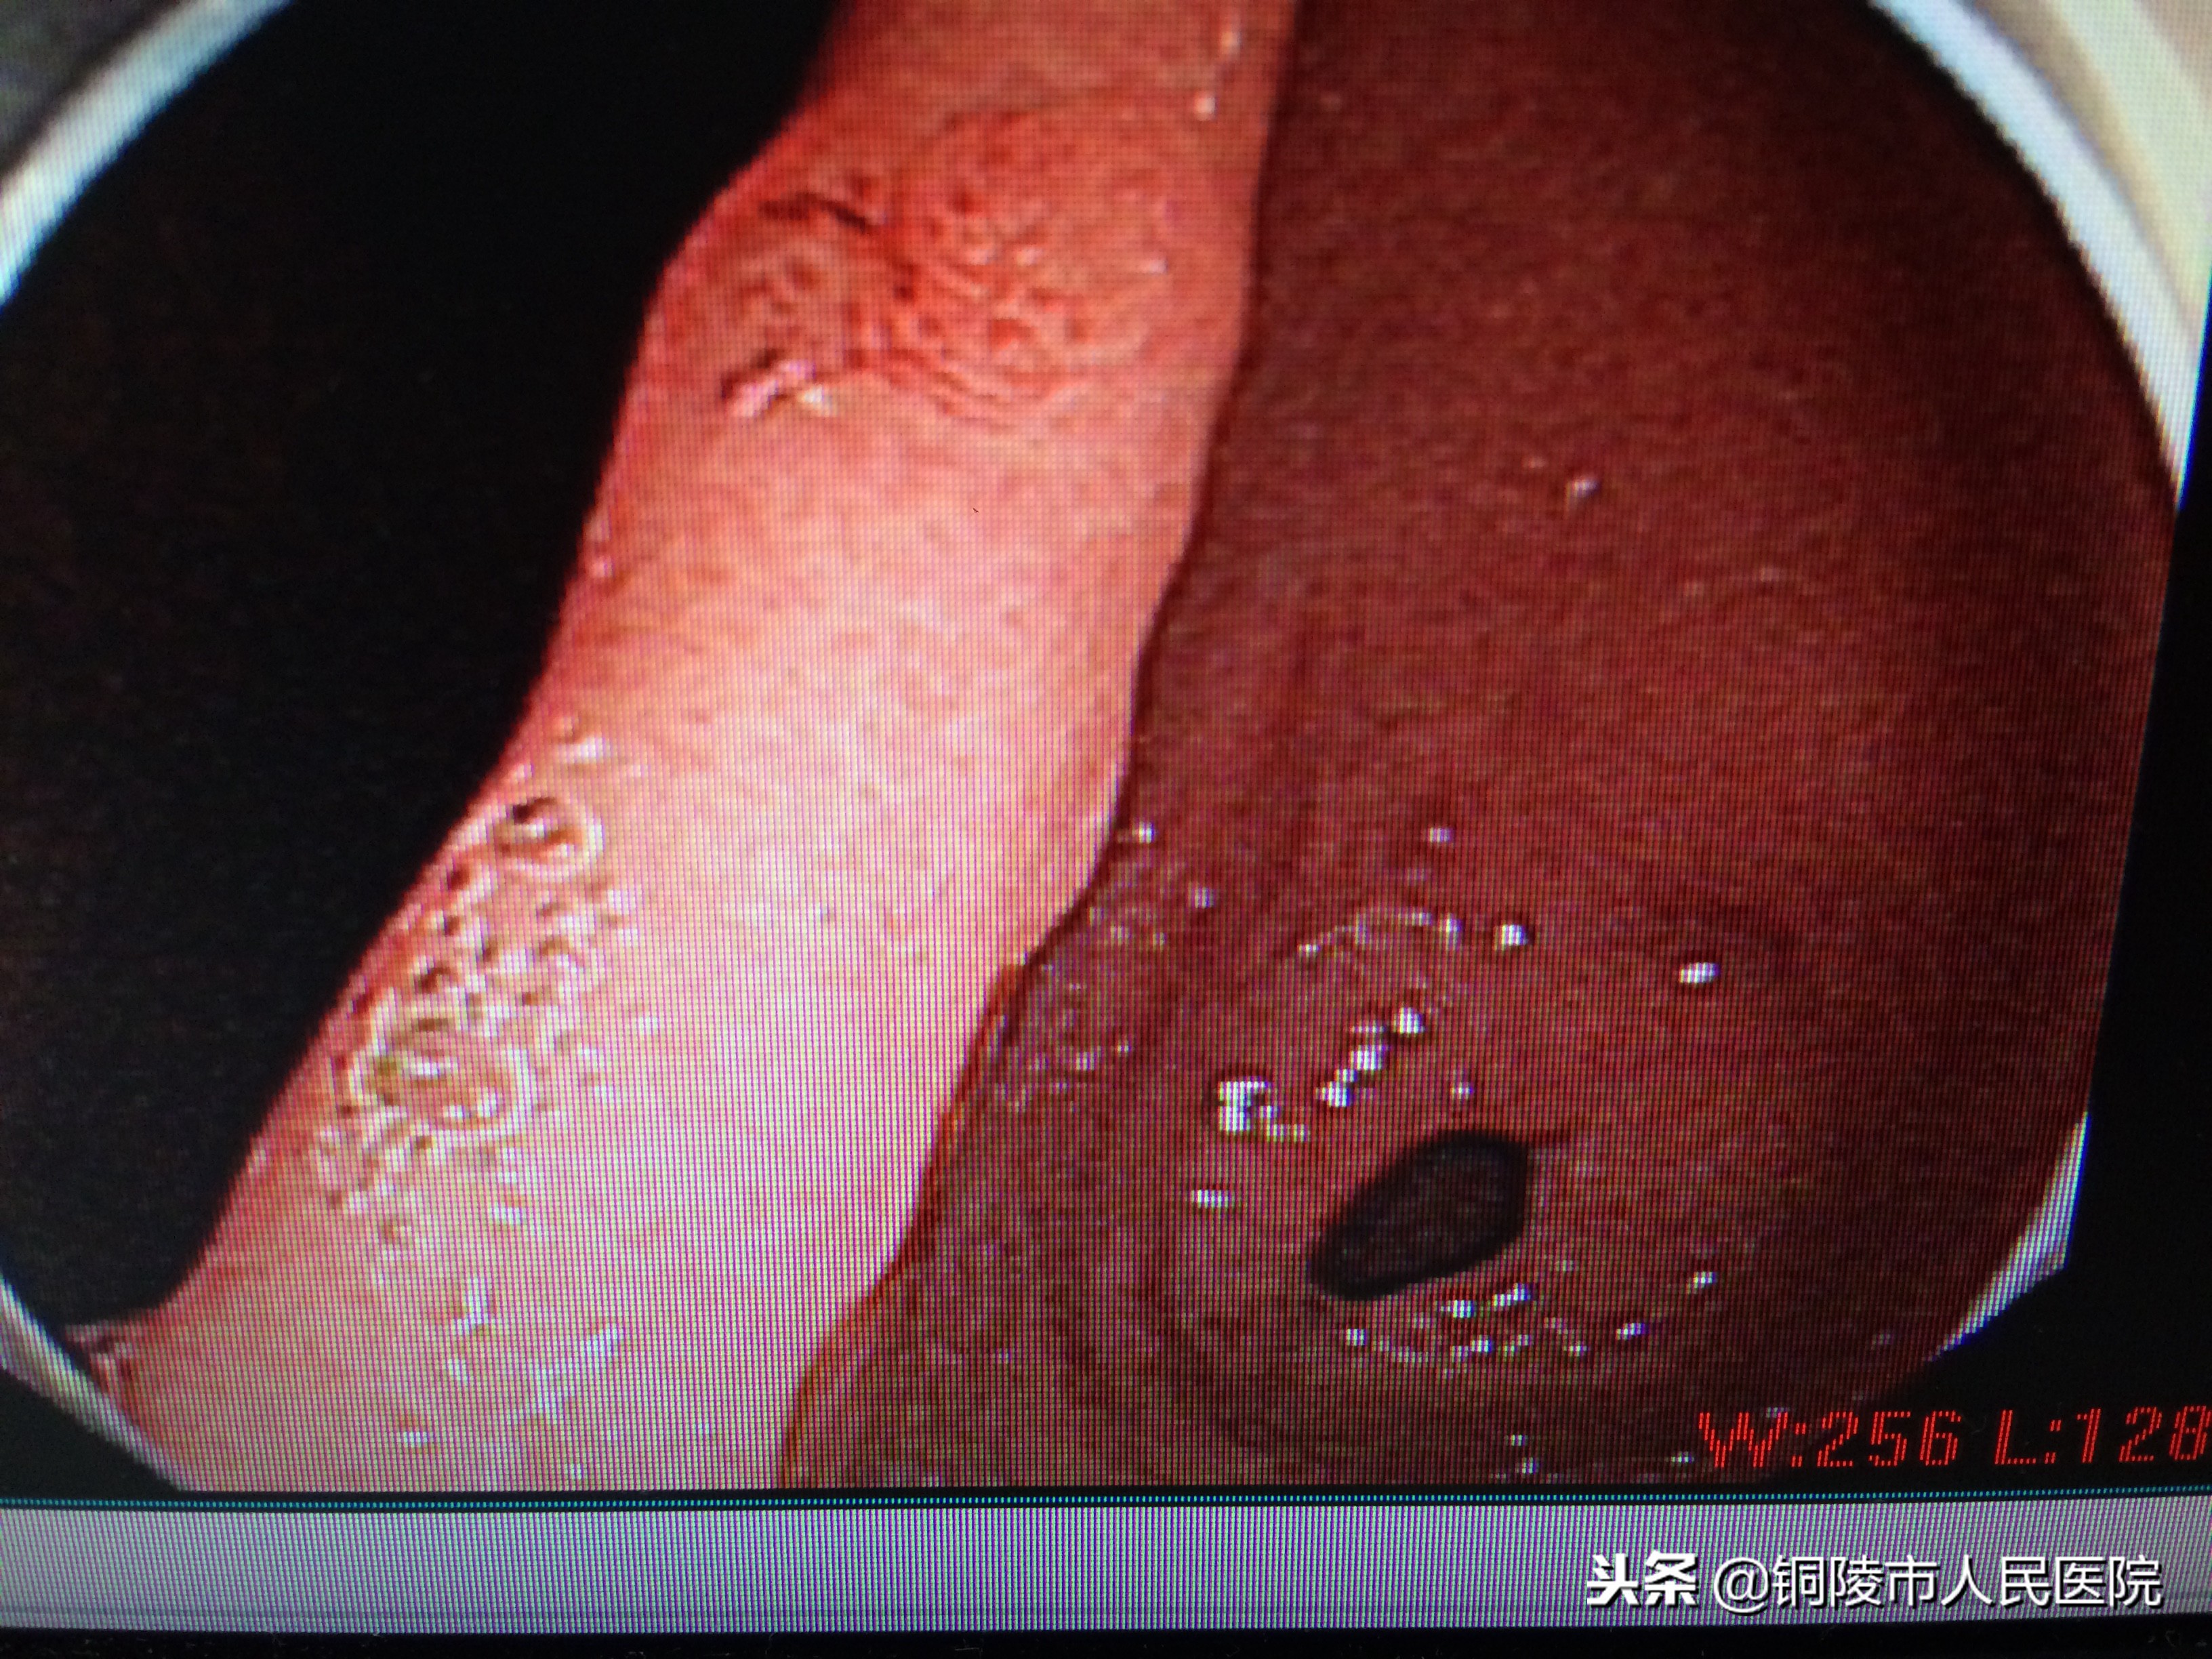

胃角早癌